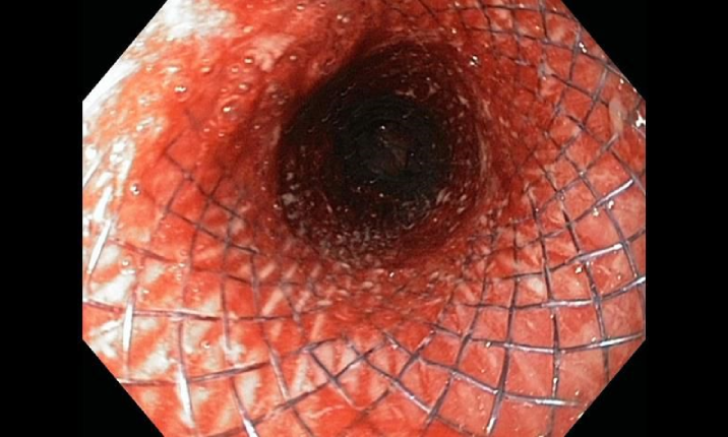

- GI stenting